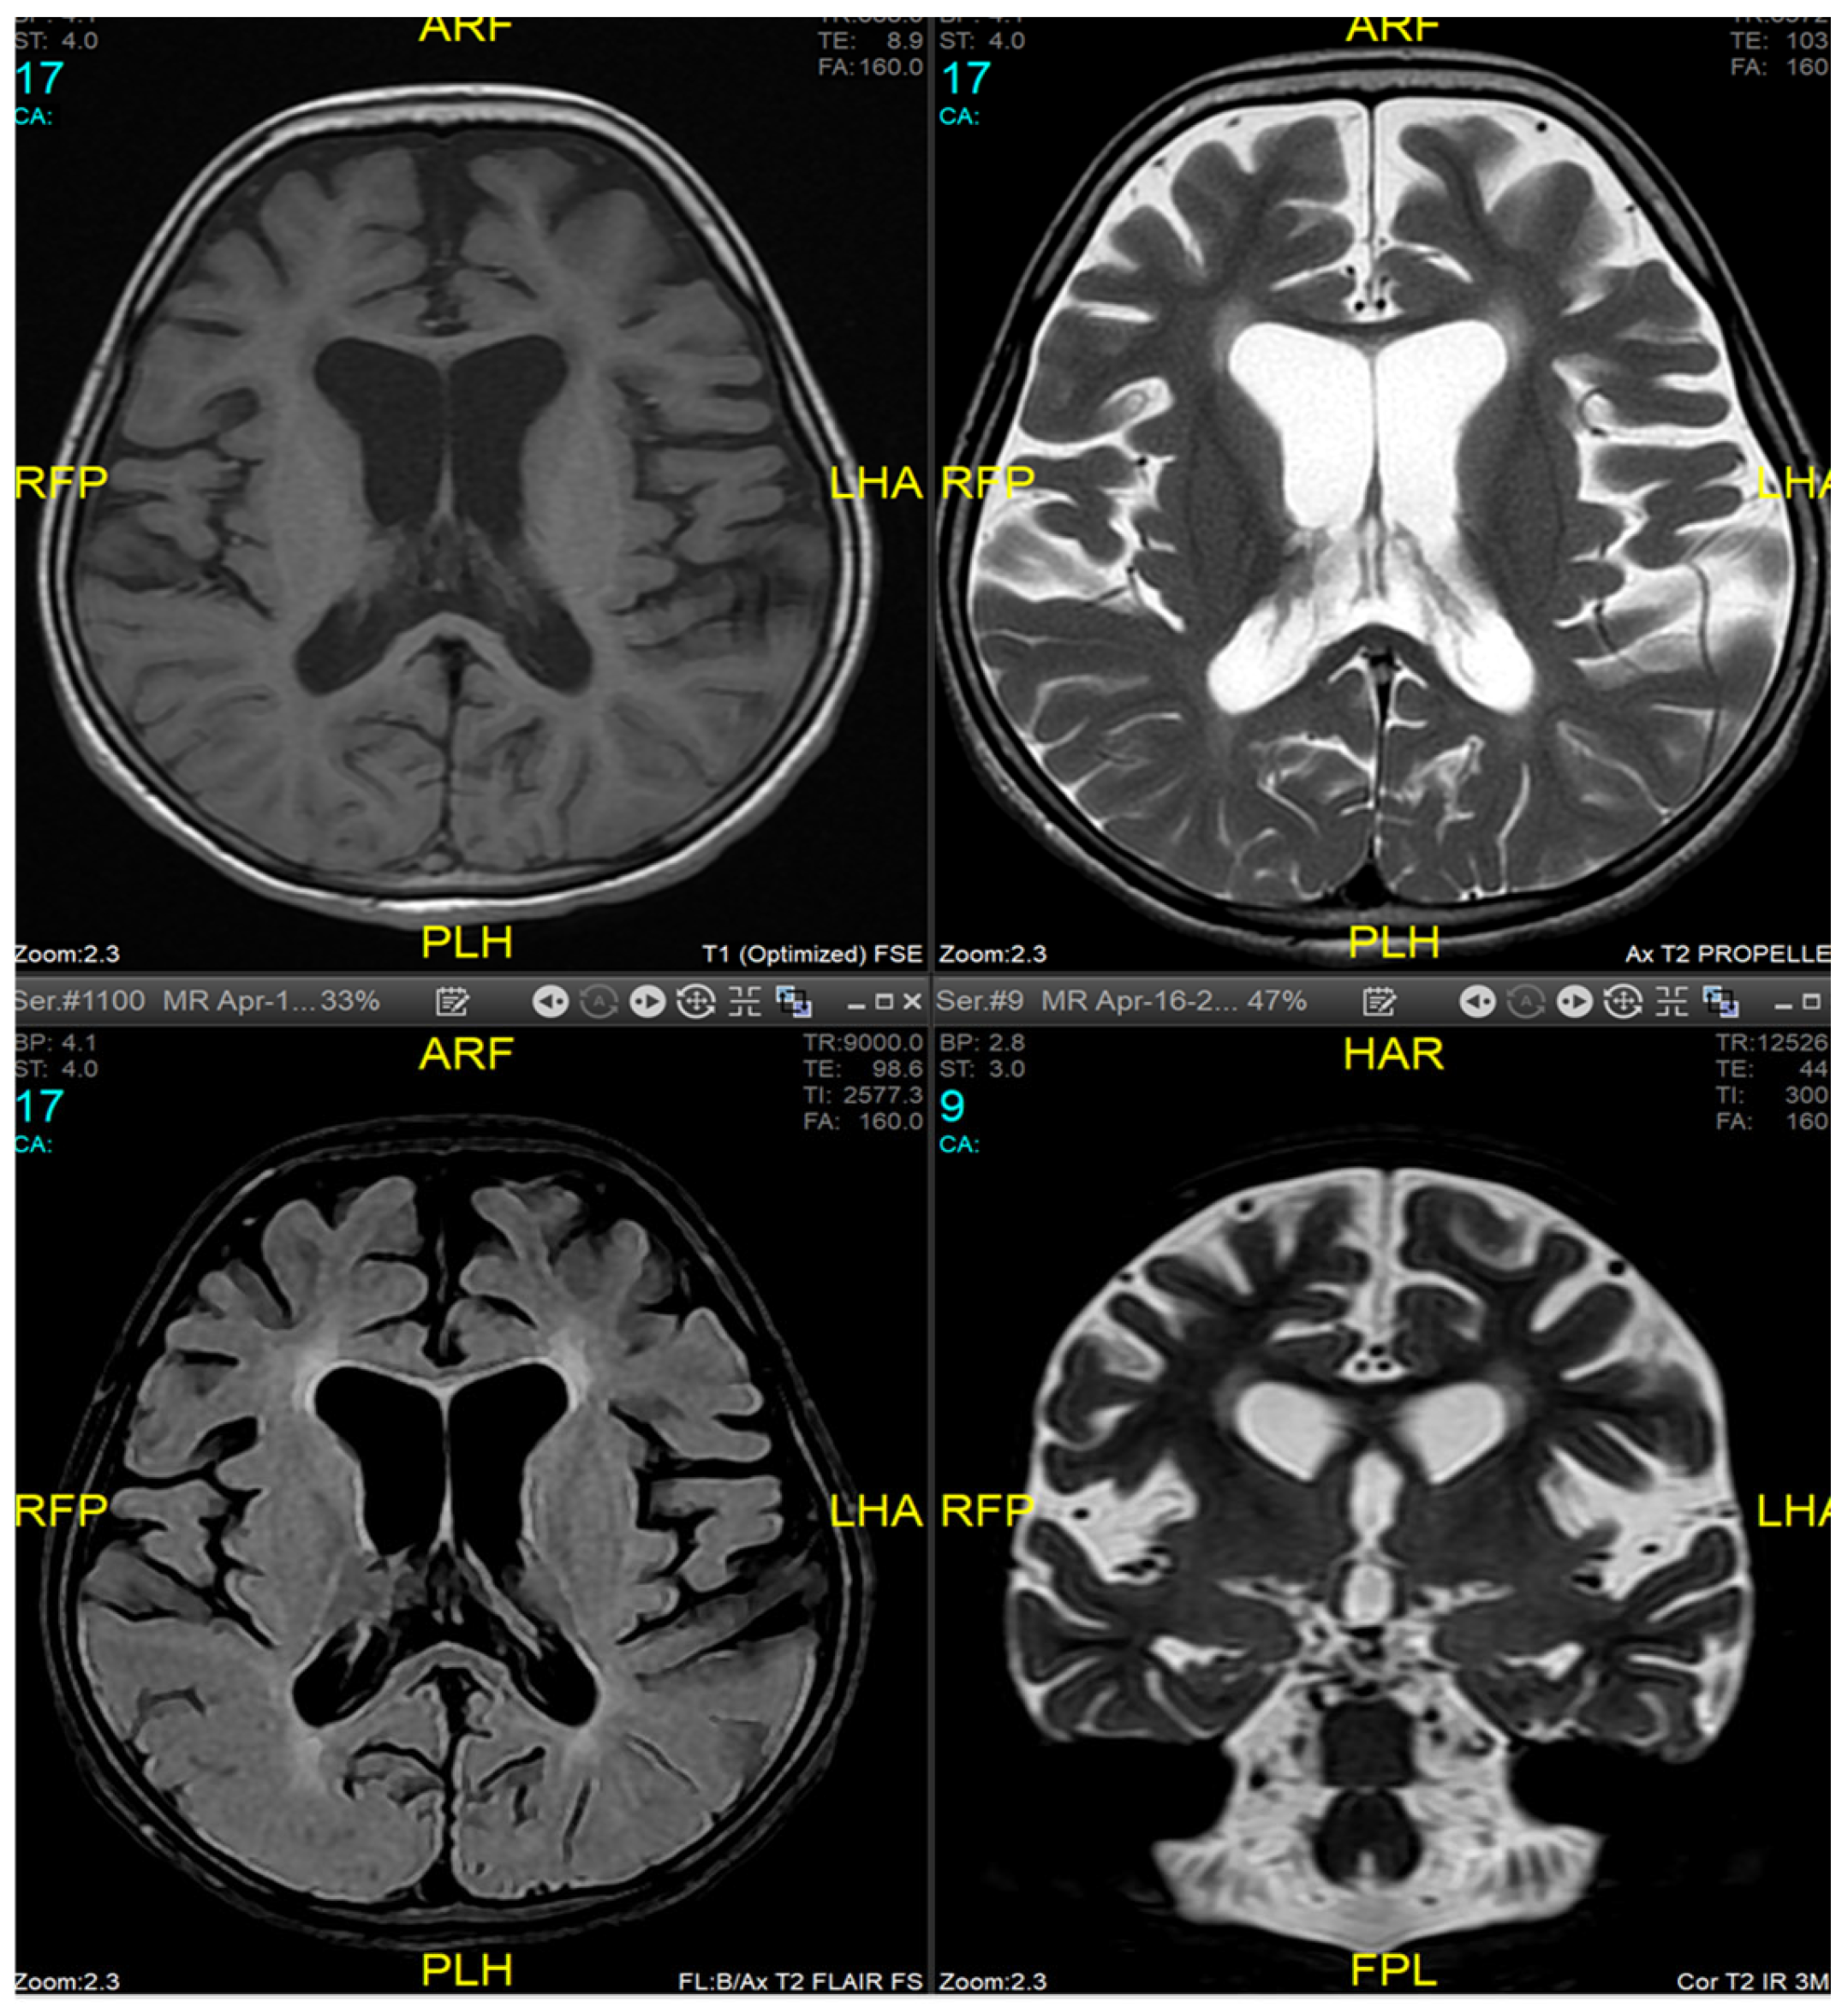

Magnetic resonance imaging (MRI) of the brain and genetic analysis were performed to support the diagnosis. Her MRI showed newly developed generalized atrophic changes of the brain, characterized by supra and infratentorial ventricular dilatation, prominent cortical sulci, and extra-axial CSF spaces such as Sylvian fissures and basal cisterns. The diffuse deep periventricular white matter showed high signal intensities on T2/FLAIR (fluid-attenuated inversion recovery) sequences. Additionally, there was global thinning of the corpus callosum [Figure 1]. This was in contrast to her prior brain MRI at 2.5 years old, which showed no evidence of atrophic brain changes or iron deposition [Figure 2].

Figure 1.

Brain MRI at 9 years of age (16 April 2024). Generalized atrophic changes of the brain, characterized by supra and infratentorial ventricular dilatation, prominent cortical sulci, and extra-axial CSF spaces such as Sylvian fissures and basal cisterns. The diffuse deep periventricular white matter showed high signal intensities on T2/FLAIR (fluid-attenuated inversion recovery) sequences. There was global thinning of the corpus callosum.

MRI findings are variable depending on the disease stage at which imaging was performed [1,3,10,12]. Imaging may be completely normal in some patients, as was the case in our patient during the first presentation, making it insufficient to rule out INAD based on radiological findings only and necessitating follow-up imaging later. Typical findings described include cerebral atrophy, white matter changes, and iron deposits in the globus pallidus, substantia nigra, and dentate nucleus [19,20]. Due to the presence of iron deposits, INAD can be classified as a subtype of neurodegeneration with brain iron accumulation diseases (NBIA). The alteration of mitochondrial functions may affect mitochondrial iron homeostasis, leading to neurodegeneration [21]. Defects in transferrin receptor recycling were established to be a common anomaly in fibroblasts from different subtypes of NBIA patients [22], suggesting impaired iron incorporation as a shared mechanism responsible for iron overload in these pathologies. However, iron deposits are not specific to INAD [23]. Our patient exhibited typical MRI features in a follow-up study but did not have any evidence of iron accumulation in the brain.